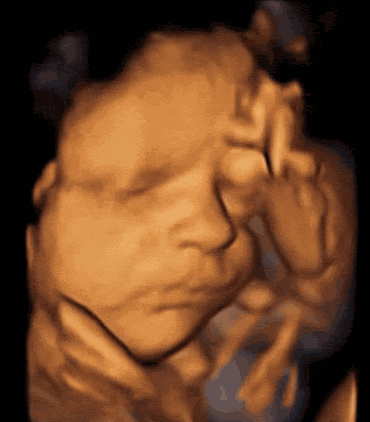

很多宝妈都知道,到了孕中期,医生都会建议做超声影像(四维彩超)排畸检查,但有不少宝妈在检查时,胎宝宝老趴着,基本上看不到五官及表情,这也让医生很头疼。虽然这种姿势是比较自然的自我保护姿势,可这样便无法筛查面部形态,也满足不了宝妈想要目睹宝宝真颜的好奇心。>>>这种情况应该怎么办呢?

福兴妇产医院是泉州地区较早引进具有“神器彩超”之称的美囯GE四维彩超的医院。美囯GE系列四维彩超以出色的成像技能、自动化辅助诊断工具、更高的硬件性能被广大孕妈和医生信赖。四维彩超能够、多角度动态显示未出生的宝宝的活动图像和人体内脏器官的图像。>>>宝宝在肚子里怎么会动?我也要一组这样的“0”岁写真